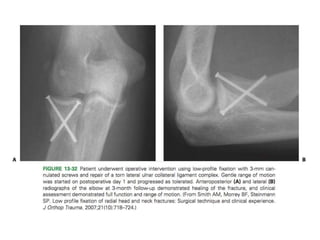

Open reduction internal fixation

of a proximal radius fracture

(A). AP radiograph of an 11-

year-old female with elbow

dislocation and radial neck

fracture

(B). Lateral radiograph of the

same patient.

C: Lateral radiograph in splint

after closed reduction showing

persistent radiocapitellar sublux-

ation. Examination under

anesthesia demonstrated very

unstable elbow joint and

therefore decision made to

proceed with open reduction

internal fixation

(D). Lateral radiograph after open

predictors of results after treatment. A higher incidence of good

Plate fixation Open reductioninternal fixation of a proximal radius fracture (A). AP radiograph of an 11- year-old female with elbow dislocation and radial neck fracture (B). Lateral radiograph of the same patient. C: Lateral radiograph in splint after closed reduction showing persistent radiocapitellar sublux- ation. Examination under anesthesia demonstrated very unstable elbow joint and therefore decision made to proceed with open reduction internal fixation (D). Lateral radiograph after open